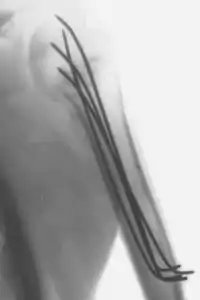

- L'enclouage : On enfonce une tige de morphologie adaptée dans le canal central d'un os long (le tibia par exemple). En formant un pas de vis, l'enclouage avec alésage peut même parfois éviter des rotations dans le foyer de fracture.